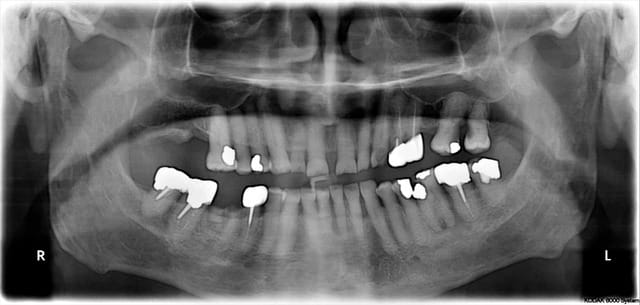

Je reçois ce patient de 80ans il y à 3 jours envoyé par son medecin generaliste pour bilan dentaire avant ttt par biphosphonate.

je lui fait une radiographie panoramique (cf pièce jointe) , et un examen clinique complet.

CAT : extraction de

racine 46

36 (nécrosé et début atteinte peri apicale)

bout de dent niveau 17

Mon soucis : Je me pose des question pour la conduite à tenir face à 16-17 : la pano et l'examen clinique montre 2 belles caries en miroir sous gingivales et avec une poche parodontale importante. Mais aucune douleurs ni mobilités.

extraire ou soigner ? je suis un peu perdu. Car si problème futur puis extraction sous BP ca va pas le faire...

c'est bon voici la panoramique !

problème de navigateur je n'avais pas le lien pour inserer les pièces jointes.

Donnez moi vos avis merci chers confrères!